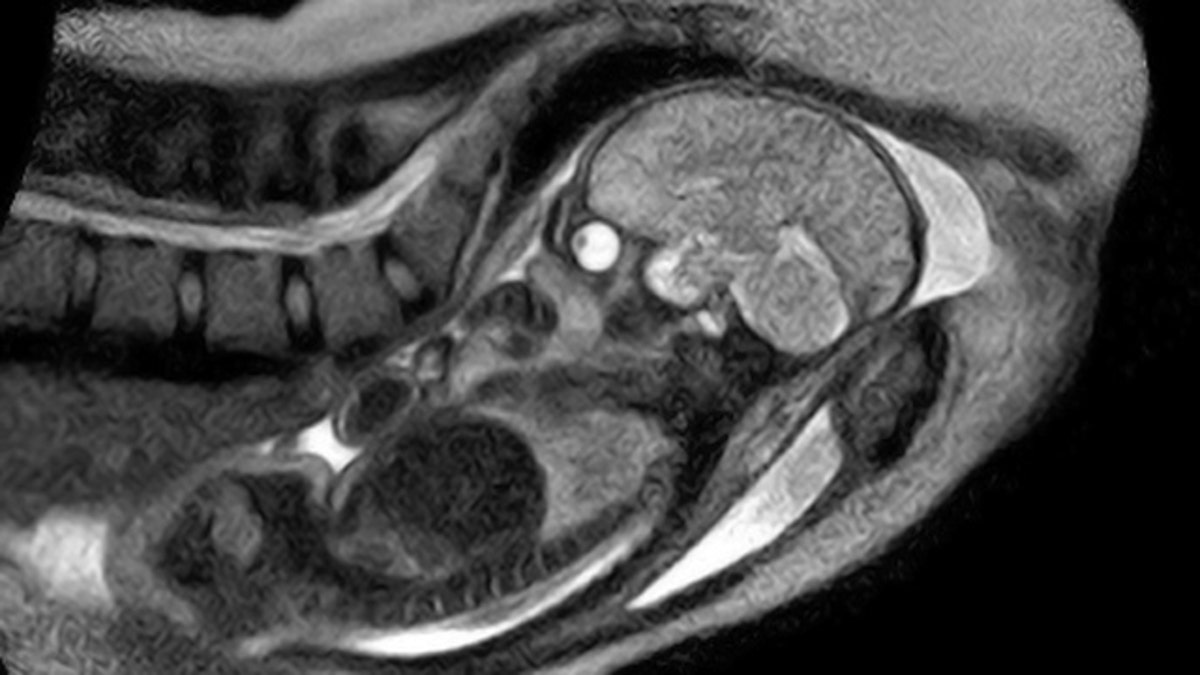

Researchers hope the new machine will allow them to study in “greater detail” how the baby moves through the birth canal, which should help them understand why a growing number of women end up needing a caesarean section. (Charité Hospital)

Doctors at a hospital in Berlin, Germany have pulled off a world first by creating MRI images of a woman giving birth, The Local Newspaper reported.

A team of obstetricians, radiologists and engineers at Charité Hospital have spent the last two years creating an “open” MRI scanner that allows a pregnant woman to fit fully into the machine to give birth. Traditional MRI machines look like long, narrow tunnels.

Researchers hope the new machine will allow them to study in “greater detail” how the baby moves through the birth canal, which should help them understand why a growing number of women end up needing a caesarean section.